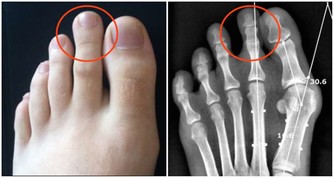

2、門靜脈高壓

表現為食道靜脈曲張,脾大和腹水,尤以食道靜脈曲張最危險。由於曲張靜脈的血管壁薄,很易破裂導致消化道大出血。